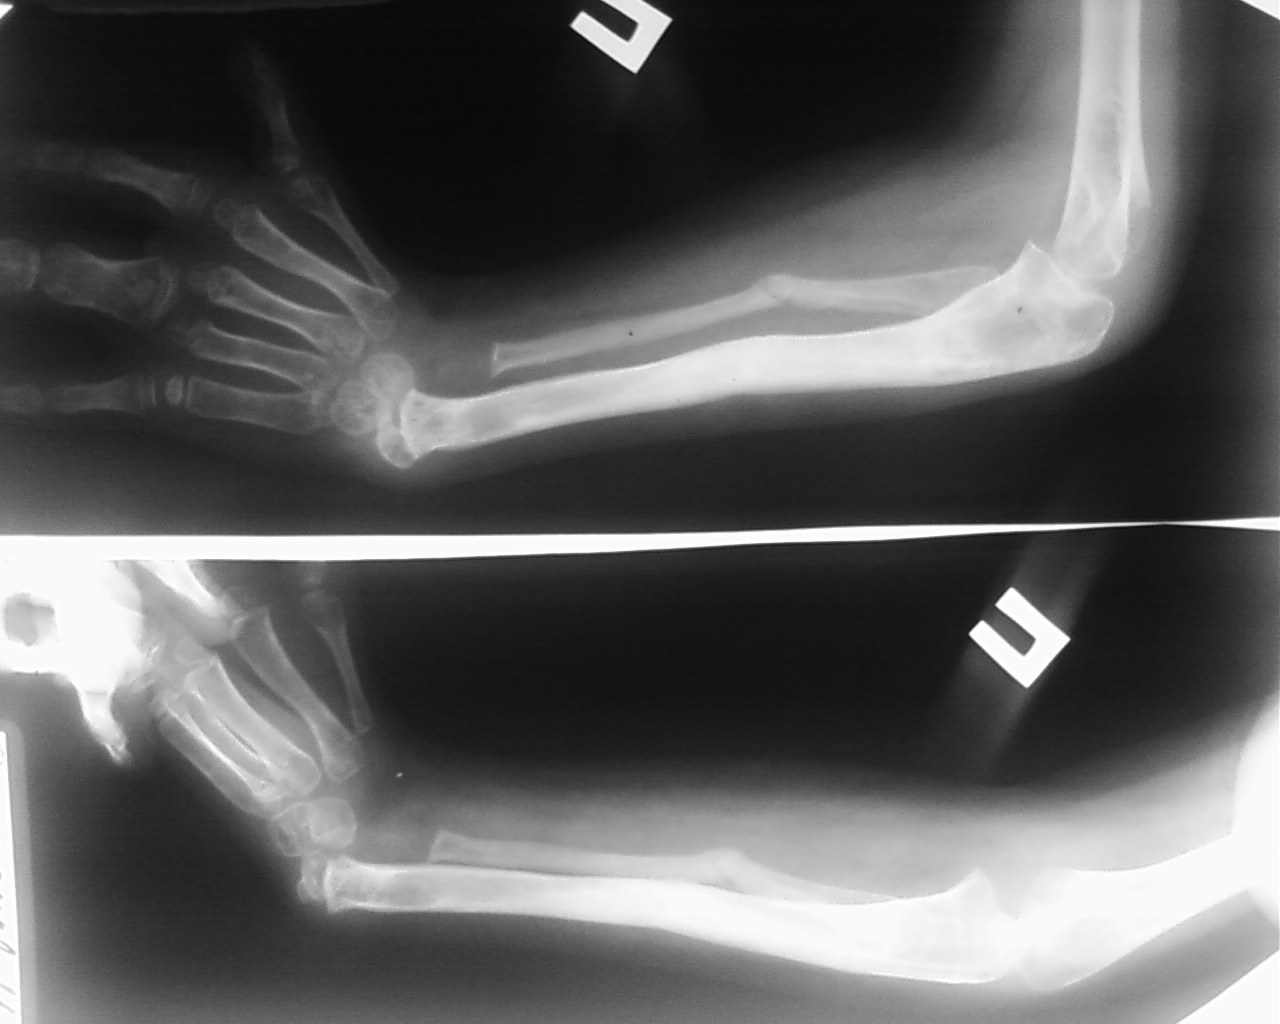

Ребёнок Д.9 лет, клинический диагноз врожденная правосторонняя лучевая косорукость первой степени.

В мае 2009 года проведено удлинение обеих костей правого предплечья в аппарате Илизарова на 4 см, в процессе дистракции был разрыв регенерата, произведена компрессия в аппарате структура кости восстановлена. Сохраняется порочное положение кисти

В настоящее время наложен аппарат внешней фиксации на правую локтевую

кость и третью пястную кость, с целью устранения порочного положения

правого кистевого сустава.Уважаемые коллеги, помогите определиться с

дальнейшей тактикой лечения данного ребенка.